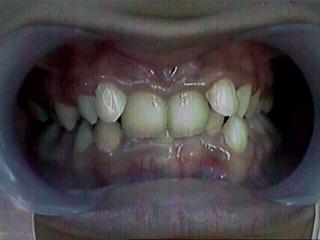

Class II Malocclusion

Malocclusion [Div.I]

Before Treatment Intra Oral